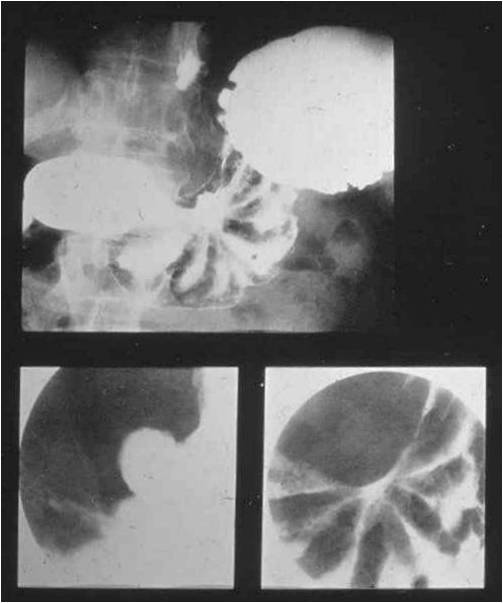

Image

Fig.26.: Napkin ring sign (or apple core sign), is a typical presentation of colon tumors.

Fig.27. Rectal cancer arising from a villous adenoma causes a rugged contour and an extensive filling defect.